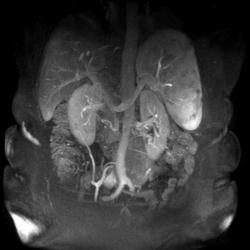

Область исследования:

Методы исследования: